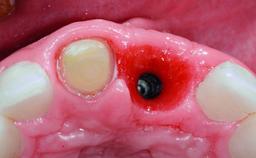

A 32-year-old female Caucasian patient with a compromised maxillary right central incisor was referred to us by a general dentist. Her chief complaints were discomfort and mobility of tooth 11 with unsatisfactory esthetics due to discoloration. The patient reported a previous trauma, some years earlier, as the origin of pathology on the afflicted tooth. Anamnesis was negative for any other dental or periodontal pathology in the remaining dentition. The patient did not take any medication and reported to be a light smoker (5–10 cigs/day). She had high esthetic expectations of her treatment. The extraoral examination revealed a high smile line with full exposure of her maxillary teeth and surrounding soft tissue in the area between the second premolars.

Case Type Single-Tooth Space

Jaw Maxilla

Area Anterior

# of Teeth 1

# of Implants 1